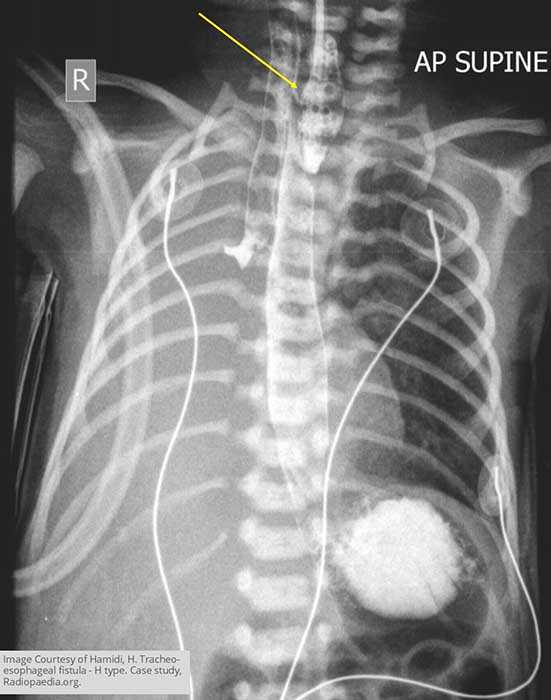

What does abdominal gas pattern indicate in TEF?

Presence or absence of bowel gas helps determine the type of TEF.

What may be seen on a plain chest X-ray for acquired tracheoesophageal fistula?

Air in the mediastinum, especially if caused by malignancy.